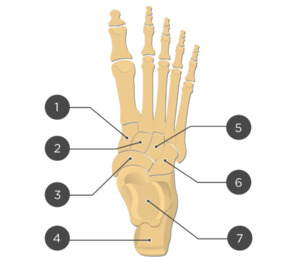

Two unlabeled illustrated images, figures 1 and 2, of the foot and one unlabeled x-ray image, figure 3, were selected. Each image was inputted into ChatGPT Version 4o and the model was prompted to identify the bones depicted in each image using the following prompt.

Prompt 2: ‘Identify the structures labeled in this image’

Two prompts were entered into ChatGPT (Prompt 1: “Make me a picture of human foot with the bones labeled”, Prompt 2: “Identify the structures labeled in this image”). Results of prompt 1, seen in figure 4, are that the generated image was detailed and visually appealing, correctly displaying a foot with visible bones as requested. However, the labeling is entirely inaccurate, with misspelled anatomical terms, misplaced labels, and several missing bones, including the phalanges of the 4th toe. The result of prompt 2 for the first illustrated image is 27% accurate with 3 of 11 bones accurately identified as shown in table 1. The result of prompt 2 for the second illustrated image is 57% accurate with 4 of 7 bones accurately identified as shown in table 2. The result of prompt 2 for the x-ray image is 0% accurate with 0 of 19 structures accurately identified as shown in table 3.

Out of 7 labels, 4 were identified correctly, resulting in an accuracy of 57%.

The output from ChatGPT v4o of prompt 1 "‘Make me a picture of human foot with the bones labeled’ demonstrates a visually appealing and detailed depiction of a human foot with visible bones. However, the labeling is inaccurate, with anatomical terms misspelled, labels misplaced, and several key bones, such as the phalanges of the 4th toe, completely missing. Prompt 2 reveals varying accuracy between the 3 images used: 27% for the first illustrated image, 57% for the second illustrated image, and 0% accuracy for the x-ray image.